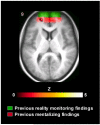

Reality monitoring refers to the process of discriminating between internally and externally generated information. Two different tasks have often been used to assess this ability: (a) memory for perceived versus imagined stimuli; and (b) memory for participant- versus experimenter-performed operations. However, it is not known whether these two reality monitoring tasks share neural substrates. The present study involved use of a within-subjects functional magnetic resonance imaging design to examine common and distinct brain mechanisms associated with the two reality monitoring conditions. The sole difference between the two lay in greater activation in the medial anterior prefrontal cortex when recollecting whether the participant or the experimenter had carried out an operation during prior encoding as compared to recollecting whether an item had been perceived or imagined. This region has previously been linked with attending to mental states. Task differences were also reflected in the nature of functional connectivity relationships between the medial anterior and right lateral prefrontal cortex: There was a stronger correlation in activity between the two regions during recollection of self/experimenter context. This indicates a role for the medial anterior prefrontal cortex in the monitoring of retrieved information relating to internal or external aspects of context. Finally, given the importance of reality monitoring to understanding psychotic symptoms, brain activity was related to measures of proneness to psychosis and schizotypal traits. The observation of significant correlations between reduced medial anterior prefrontal signal and scores on such measures corroborates these theoretical links.